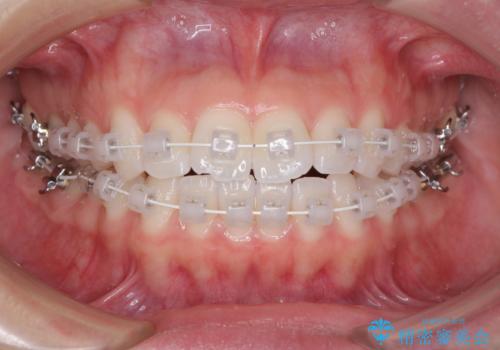

- 矯正装置

- 審美装置

治療開始から4ヶ月ほどで概ね歯列が整い、その後の3ヶ月で細かい部分を仕上げていきました。

短期間で綺麗に仕上がり、患者様には大変満足していただきました。